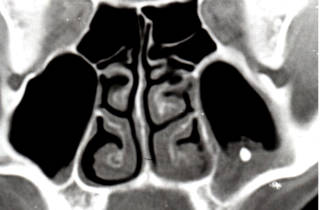

Врачи отмечают, что наличие инородного тела в гайморовой пазухе может привести к серьезным осложнениям. Чаще всего такие случаи возникают после травм, хирургических вмешательств или при попадании посторонних предметов, например, во время занятий спортом. Симптомы могут варьироваться от легкого дискомфорта до выраженной боли, отечности и затрудненного дыхания. Важно, что своевременная диагностика и лечение играют ключевую роль в предотвращении инфекций и других осложнений. Врачи рекомендуют при подозрении на инородное тело обращаться за медицинской помощью, так как самостоятельные попытки удаления могут усугубить ситуацию. Современные методы визуализации, такие как КТ, позволяют точно определить местоположение и характер инородного объекта, что значительно облегчает дальнейшее лечение.

Если вы заметили указанные симптомы или не можете справиться с хроническим гайморитом, рекомендуется пройти полное диагностическое обследование. Этот процесс включает несколько этапов:

- при необходимости – компьютерная томография.